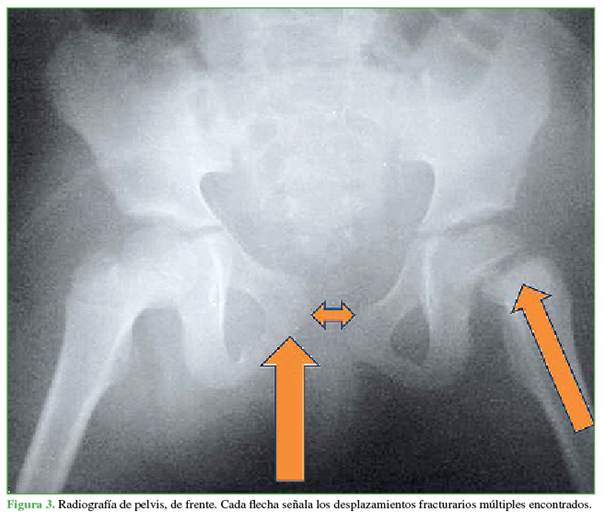

De todas las radiografías solicitadas la de pelvis de frente reveló fracturas compatibles con politraumatismo (Figura 1). Se observa una fractura de pelvis tipo C según la clasificación AO, más una avulsión del ala ilíaca y una fractura tipo A de la misma clasificación.1 En la epífisis femoral proximal izquierda, se constató una epifisiólisis tipo I (transepifisaria) según la clasificación de Delbet (Figuras 2 y 3).2